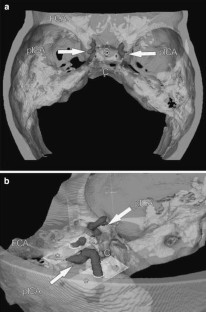

Three-dimensional (3D) computer models, reconstructed from contrast enhanced computed tomography (CT) data of 30 randomly selected patients (60 pICAs) were analyzed with modern visualization software and new mathematical algorithms. As objective measures for the pICA shape complexity, we provide calculations of curvature energy, torsion energy, and total complexity of 3D skeletons of the pICA lumen. We further measured the posterior knee of the so-called “carotid siphon” with a virtual goniometer and performed correlations between the objective mathematical calculations and the subjective angle measurements.

Firstly, our study provides mathematical characterizations of the pICA shape, which can serve as objective reference data for analyzing connections between pICA shape complexity and vascular diseases. Secondly, we provide an objective method for creating such data. Thirdly, we evaluate the usefulness of subjective goniometric measurements of the angle of the posterior knee of the carotid siphon.